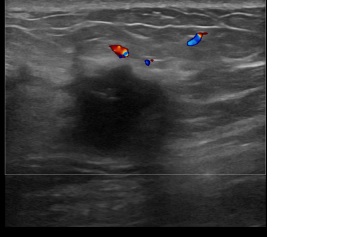

상기환자는 우측유방 단단함과 유두함몰로 진료위해 내원하신 60대초반

여성분으로 의심스러운 우측혹 조직검사 시행해 유방암 진단되었습니다.